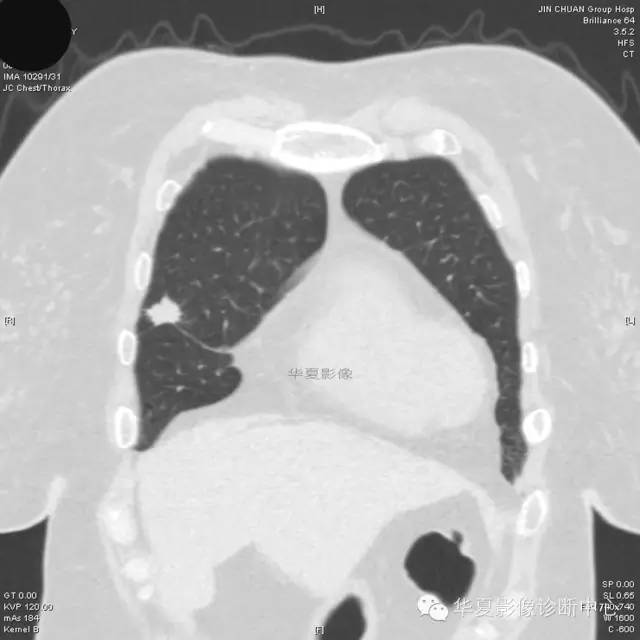

【病例学习】典型周围型肺癌CT病例一例

女,56岁,其父因肺癌去世,自觉胸部疼痛不适来诊要求拍胸片。

1.右肺上叶:肺组织1块,大小13×4×7cm。切面棕红色。2.右肺上叶肿物:灰白色组织一块,大小3×1×1.5cm。切面灰白色。3.右肺中叶结节:灰白色绿豆大组织1块。4.淋巴结:灰黑色绿豆大组织1块。

(右)肺中分化鳞状细胞癌。浸及胸膜。支气管残端切净。淋巴结未见癌转移(0/10)。